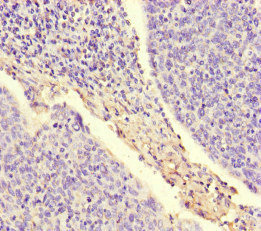

Immunohistochemistry of paraffin-embedded human cervical cancer using CSB-PA01679A0Rb at dilution of 1:100